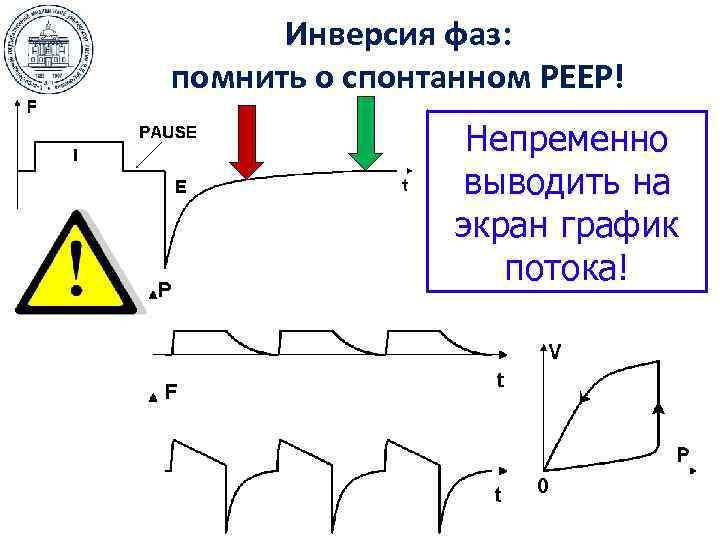

Инверсия фаз: помнить о спонтанном РЕЕР! Непременно выводить на экран график потока!

Инверсия фаз: помнить о спонтанном РЕЕР! Непременно выводить на экран график потока!